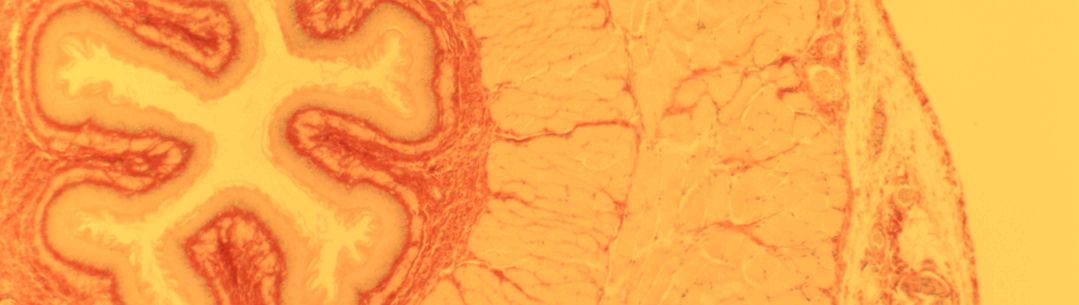

By studying the role of the vagal system in the control of energy metabolism - understanding which nerve signals suppress or elicit food satiety - we can design efficient treatments for obesity.

By studying the role of the vagal system in the control of energy metabolism - understanding which nerve signals suppress or elicit food satiety - we can design efficient treatments for obesity.

We aim to develop an accurate system for detection, stimulation and recording of chemical and electrical changes in the vagus nerve in response to physiological stimulation of gut hormones and nutrients.